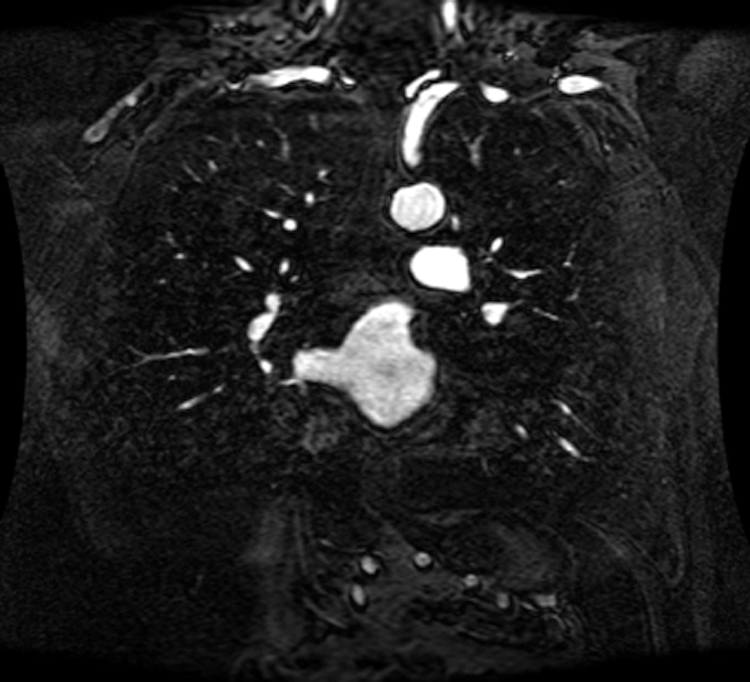

An intelligent-MRI VLC has been implemented for MRI image transmission using VLC and RF interference is eliminated. The proposed intelligent-MRI VLC system is experimentally analyzed using MRI images of different sizes i.e., 100, 115, and 120 KB respectively. These MRI images of the chest are downloaded from a medical database physionet.org. The downloaded MRI images are of T1 weighted type, which has grey matter darker than white matter was used for the proposed work. Images are acquired using Image Acquisition (IMAQ) in LabVIEW and transmitted using visible light in an indoor environment. The downloaded MRI images of various sizes are shown in Figs. 13–15.

Figure 14: 115 KB MRI image